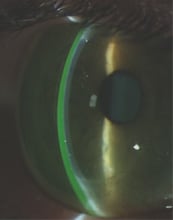

Corneal topography has revolutionized the detection of keratoconus and was addressed in detail at the GKC. Tim McMahon, OD, FAAO, presented data from the Collaborative Longitudinal Evaluation of Keratoconus (CLEK) study, whose researchers developed a special tool to create a new index to help analyze and categorize keratoconus. They introduced The Cone Location and Magnitude Index (CLMI) based on tangential maps to document the exact location of the apex of the cornea. Based on the analysis of 838 corneas, they found that in 87.8 percent of cases the apex was located beneath the horizontal central line on the cornea and that in only 10 percent to 12 percent of cases was the apex above that line. They observed a nipple cone (3mm in diameter, Figure 1) in 28.7 percent of cases, an oval cone (3.0mm to 5.5mm) in 44.3 percent of cases and a globus cone (5.0mm and larger) in 6.7 percent of cases. They defined a new type of cone as a marginal cone shape, which Dr. McMahon described as located at 270 degrees around the marginal limbus and prevalent in 5.6 percent of cases. The remaining 11 percent of cones remained undefinable.

Figure 1. A keratoconic eye with a nipple cone. Photo courtesy of R. Visser, Visser Contact Lens Practice.